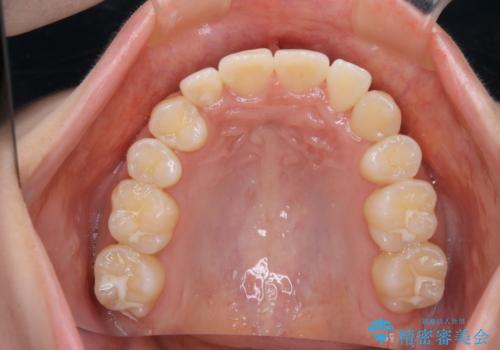

開窓して器具で力をかけても動く様子がなかったため抜歯とし、小臼歯を犬歯に見立てて治療を完了しました。

結果的に見た目の違和感もなく、期間の短縮にもつながりました。

- 治療期間

- 1年6ヶ月